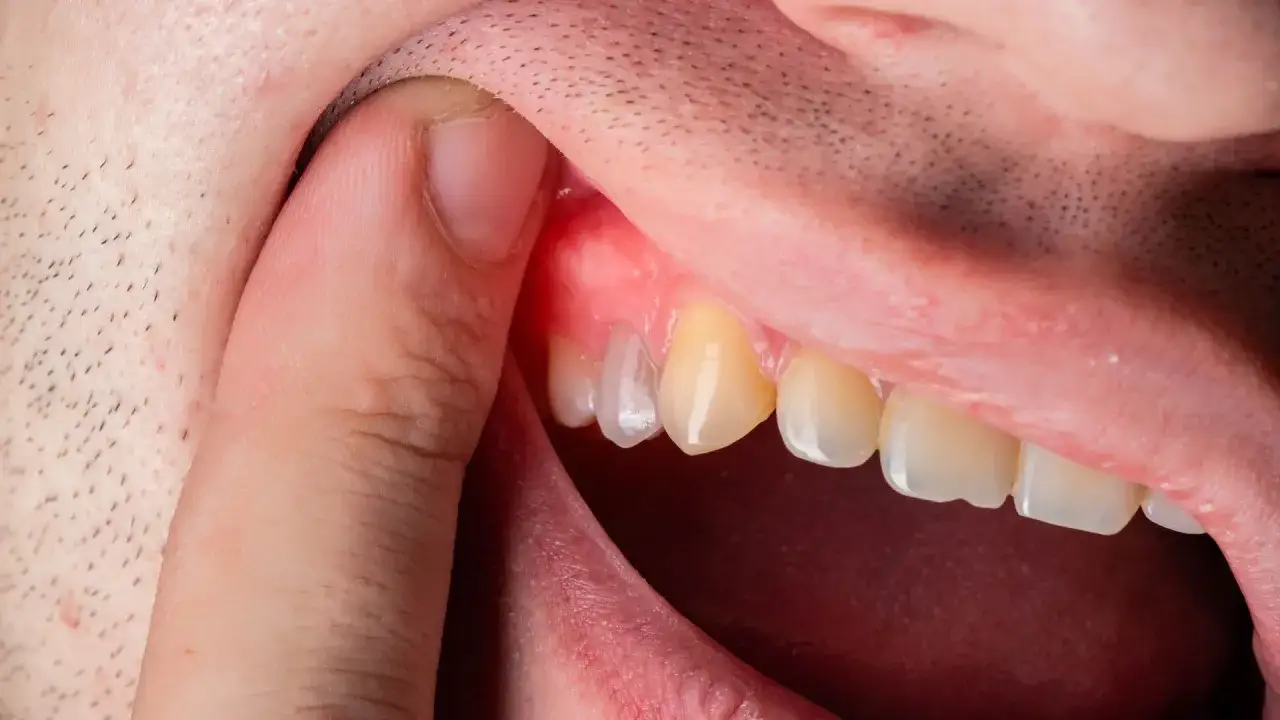

Obrzęk dziąsła w okolicy jedynek, czyli zębów siecznych, jest dość powszechnym zjawiskiem, które może mieć wiele przyczyn. Od łagodnych stanów zapalnych, będących wynikiem niedostatecznej higieny, po poważne infekcje wymagające pilnej interwencji stomatologicznej. Kluczowe jest zwrócenie uwagi na charakter zmiany: czy guzek jest miękki i bolesny, czy może twardy i nieruchomy? Czy krwawi podczas szczotkowania, czy też jest bezobjawowy? Te obserwacje pomogą wstępnie ocenić sytuację.

Obrzęk może być lokalnym stanem zapalnym, infekcją bakteryjną, podrażnieniem mechanicznym, a nawet, w rzadszych przypadkach, łagodną zmianą kostną na podniebieniu. Nie każdy obrzęk jest powodem do paniki, ale każdy wymaga uwagi i często konsultacji ze specjalistą. Moim zdaniem, nigdy nie należy lekceważyć sygnałów wysyłanych przez nasz organizm, zwłaszcza w tak delikatnej okolicy jak jama ustna.

Ropień zęba lub ropień dziąsła w okolicy siekacza

Ropień to poważna infekcja bakteryjna, która wymaga natychmiastowej interwencji. Ropień zęba (okołowierzchołkowy) rozwija się w wyniku martwicy miazgi zęba, często spowodowanej głęboką próchnicą lub urazem. Ropa gromadzi się u wierzchołka korzenia i może przebić się przez kość, tworząc obrzęk na dziąśle. Ropień dziąsła (periodontalny) natomiast powstaje w wyniku infekcji w kieszonce dziąsłowej, czyli przestrzeni między zębem a dziąsłem, często u osób z zaawansowaną chorobą przyzębia. Oba stany charakteryzują się silnym bólem, obrzękiem i często obecnością ropy.

Objawy sugerujące ropień lub szerzącą się infekcję

- Silny, pulsujący ból, który może promieniować do ucha, szczęki lub szyi.

- Obecność ropy – może być widoczna jako białawy guzek, z którego sączy się płyn, lub odczuwalna jako nieprzyjemny posmak w ustach.

- Gorączka, dreszcze lub ogólne złe samopoczucie.

- Obrzęk rozprzestrzeniający się na wargę, policzek, a nawet całą twarz.

- Trudności w otwieraniu ust (szczękościsk), połykaniu (dysfagia) lub oddychaniu.

- Dziąsło jest bardzo tkliwe na dotyk.

Ropień zęba lub dziąsła nie ustępuje samoistnie i może się szerzyć, prowadząc do poważnych komplikacji zdrowotnych.